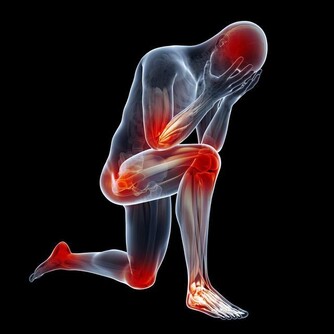

長期慢性智齒冠周炎還可能成為病灶感染的來源,導致關節炎或關節膿腫或其他器官的膿腫,甚至會導致心肌炎的可能。

某些智齒還可能導致開口困難或神經痛。